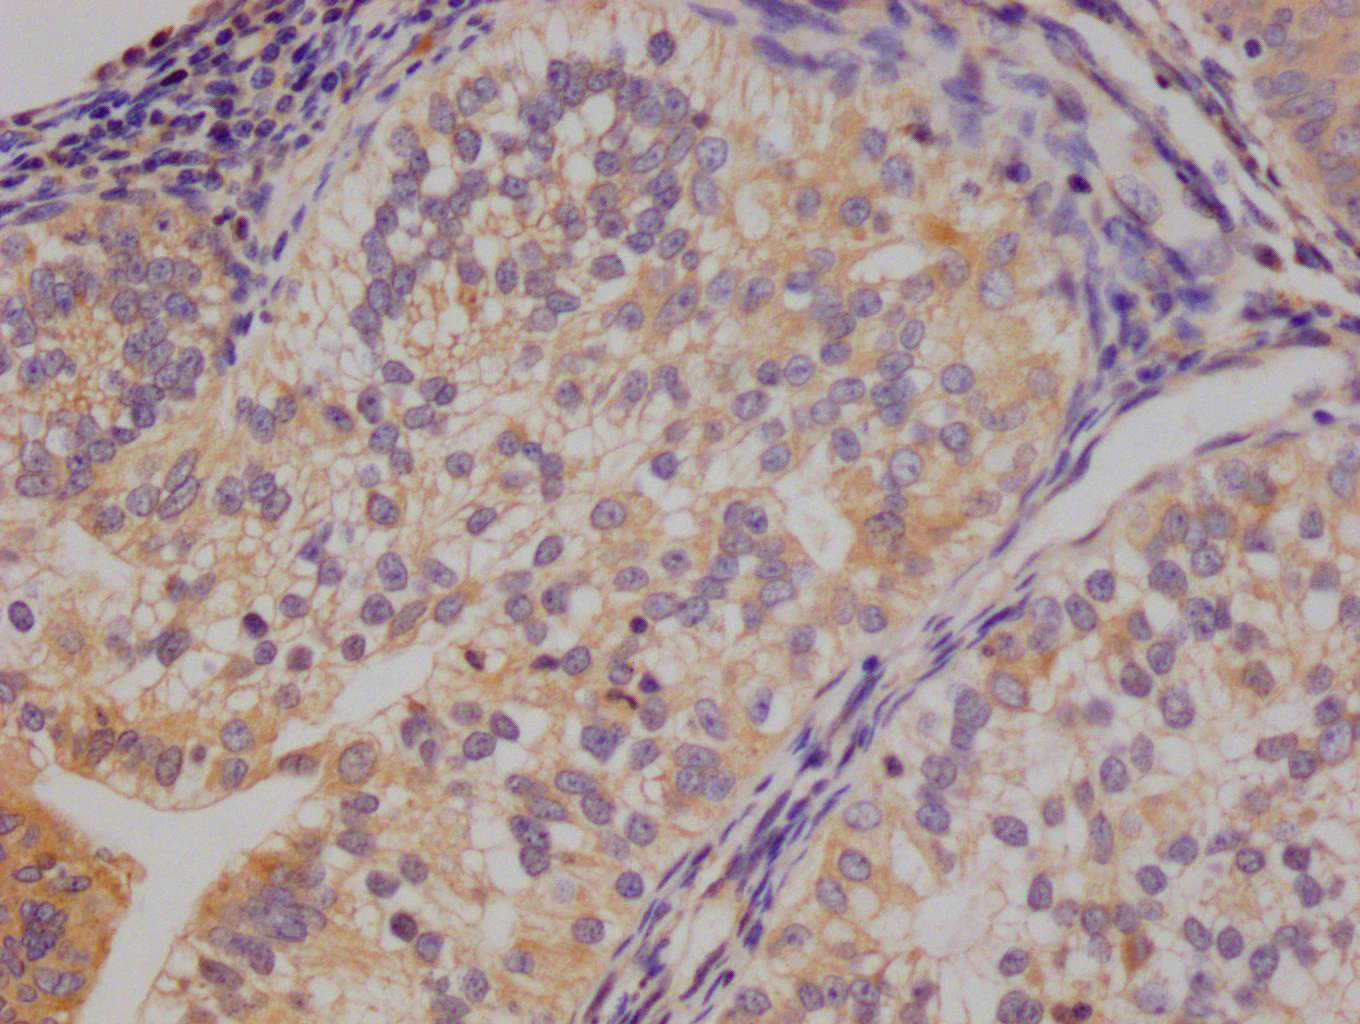

Immunohistochemical analysis of paraffin-embedded Human Colon Carcinoma Tissue using HSP40 Rabbit pAb diluted at 1:200